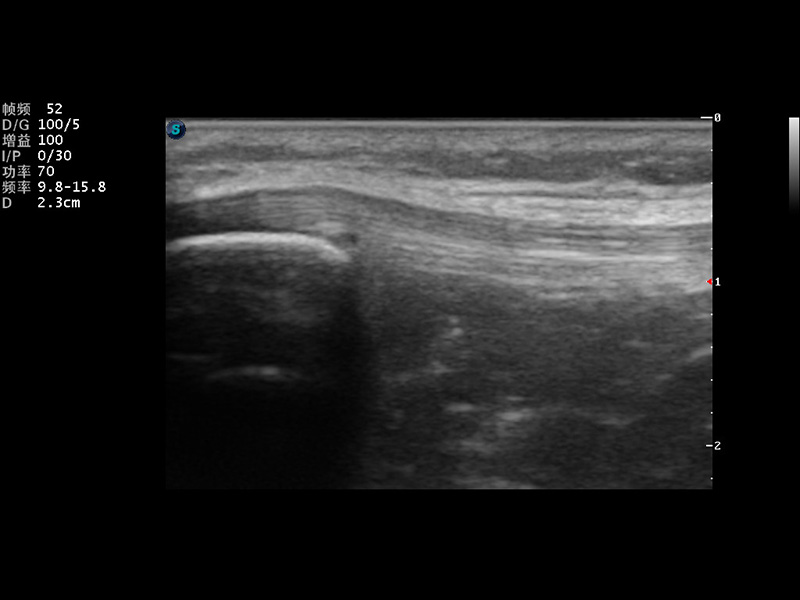

S9便携式彩色多普勒超声诊断仪是16877太阳集团研发的高端便携彩超设备,外观设计新颖、产品性能卓越。S9在便携超声领域采用了突破传统的触摸屏交互设计,并以先进的软件硬件技术和设计理念,为您带来清晰的图像质量、稳定的工作性能和便捷的操作体验。

μ-Scan微米成像